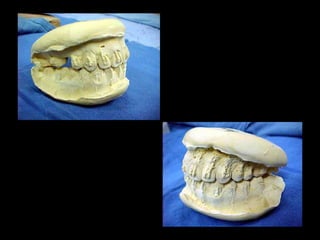

Modelos PreoperatoriosModelos Preoperatorios

Arcada Superior:

Forma oval

Paladar profundo

Totalidad de órganos dentarios a excepción de tercer molar izq.

Restauraciones deficientes

Arcada Inferior:

Forma ovalada

Colapso posterior

Ligero apiñamiento de anteriores

Rotación de premolares

Modelos vista lateral

prequirúrgica

Clase III molar y caninaClase III molar y canina

Arcada Superior: Forma oval Paladarprofundo Totalidad de órganos dentarios a excepción de tercer molar izq. Restauraciones deficientes Arcada Superior: Forma oval Paladar profundo Totalidad de órganos dentarios a excepción de tercer molar izq. Restauraciones deficientes Frente: Línea media desviada Mordida cruzada anterior Frente: Línea media desviada Mordida cruzada anterior Arcada Inferior: Forma ovalada Colapso posterior Ligero apiñamiento de anteriores Rotación de premolares Arcada Inferior: Forma ovalada Colapso posterior Ligero apiñamiento de anteriores Rotación de premolares

Modelos vista lateral prequirúrgica Modelosvista lateral prequirúrgica 6 6 3 3 Clase III molar y caninaClase III molar y canina